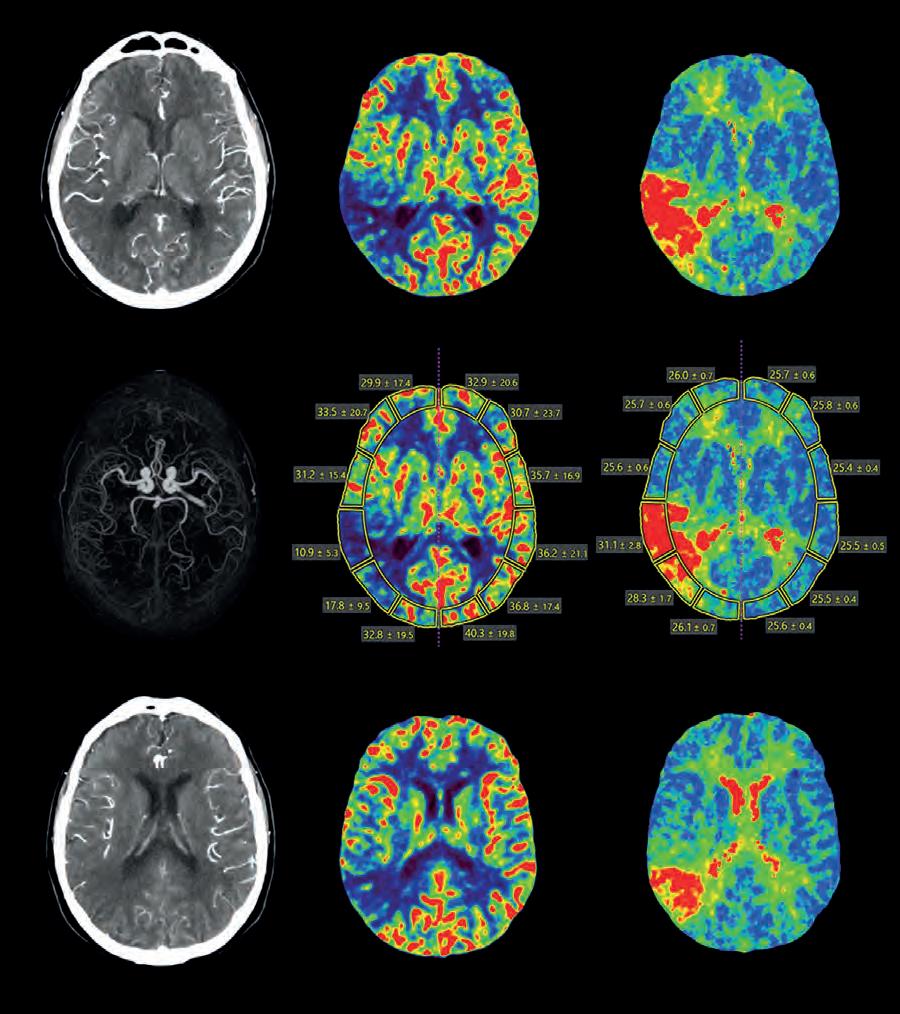

Fig

1. Carotid Angiography using AI-assisted CT: Low-dose Ultra Helical CT Angiogram of the Carotids and Circle of Willis for stroke work-up.

AI-assisted

CT provides clear visualisation of contrast enhanced vessels and surrounding soft tissue for fast and confident rule-out of occlusion.

Diagnostic Imaging Insights Accelerated by Artificial Intelligence

Mark Hitchman, Managing Director of Canon Medical Systems UK, highlights the exciting AI innovations in diagnostic imaging and discusses the need for home-grown data to power advancements in the future

Artificial

Intelligence (AI) in healthcare is big news. Nearly every day there is a new study or research result announced, powering the potential advances in how we diagnose, treat and prevent healthcare conditions in the future. It stirs the imagination and is an exciting exploration to be part of, but it also has to be a manageable process, realistic and scalable.

With every positive news story on the advances of AI in healthcare, there is also the counterbalance that questions when we will realistically be able to use these advancements in clinical practice. Our response is that AI is already here. It's being used in many hospitals and clinics up and down the UK, perhaps without the radiographers even realising, as it works seamlessly behind the scenes.